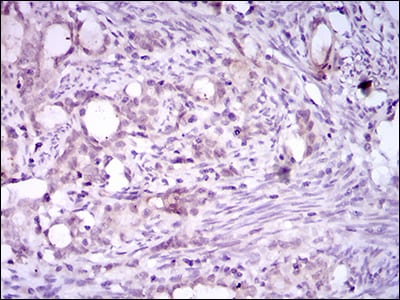

分类: 科研抗体货号: 30507别名: FLK2; STK1; CD135; FLK-2应用: IHC反应种属: Human